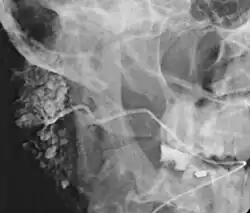

![]() Sialogram in a patient suspected of Sjögren's syndrome | |

This procedure is indicated when there is recurrent swelling and pain on the face but ultrasound has not revealed any problems. If Sjögren syndrome (also known as Sicca syndrome, an autoimmune disease that affects the lacrimal and salivary glands, causing reduced tears and saliva production) is suspected, this procedure is useful. Besides, when interventional procedure is planned such as stone removal from salivary ducts or dilatation of the strictures in the salivary gland, this procedure is also indicated.[4] However, for those who are pregnant, with allergy to iodinated contrast, and ongoing infection or inflammation of the face, the procedure is contraindicated.[4]

This study is interpreted by evaluating the morphology of the salivary ducts for obstructions and chronic inflammation. Sialodochitis is a term describing dilation of the ducts caused by repeated inflammatory or infective processes. There is also irregular salivary duct stricture (narrowing) of the duct, which creates an appearance known as "sausage link" pattern on a sialogram. Suggestions of abscesses and autoimmune diseases such as Sjögren syndrome can also be elicited. Sialadenitis is inflammation of the salivary glands, which may cause acinar atrophy and create an appearance known as "pruning of the tree" on a sialogram, where there are less branches visible from the duct system. A space occupying lesion that occurs within or adjacent to a salivary gland can displace the normal anatomy of the gland. This may create an appearance known as "ball in hand" on an sialogram, where the ducts are curved around the mass of the lesion.[6]